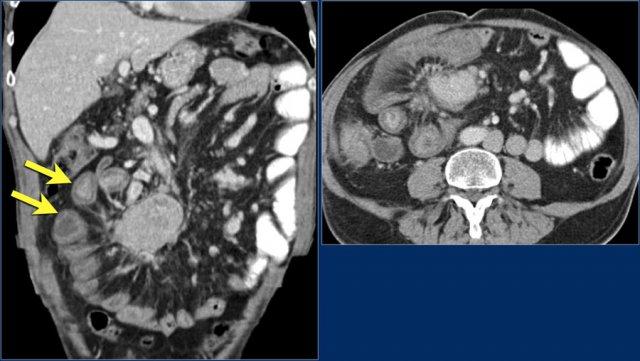

Đây là hình ảnh điển hình của u carcinoid biểu hiện là một khối mạc treo lớn với phản ứng xơ hóa desmoplastic và co kéo các quai ruột non lân cận kèm dày thành ruột (các mũi tên).

U carcinoid có vôi hóa và phản ứng xơ hóa desmoplastic. Tắc ruột non do thành phần trong lòng ruột của u carcinoid. Lưu ý tổn thương di căn gan nhỏ (mũi tên).

Các hình ảnh cho thấy u carcinoid biểu hiện là một khối tăng sinh mạch (mũi tên đỏ) với phản ứng xơ hóa desmoplastic (mũi tên vàng).

U carcinoid là các khối u phát triển chậm, có thể không được phát hiện trong nhiều năm.

Chúng khởi phát là các tổn thương dưới niêm mạc nhỏ (hình ảnh).

Khi u carcinoid phát triển, thành ruột dày lên, cuối cùng dẫn đến xâm lấn ra ngoài thành ruột.

U carcinoid có thể gây ra phản ứng xơ hóa desmoplastic mạnh với co kéo các quai ruột và xơ hóa, đôi khi dẫn đến thiếu máu ruột.

Tuy nhiên, khi u carcinoid còn nhỏ, các dấu hiệu thường không đặc hiệu.

Khối u có thể biểu hiện là một nốt dưới niêm mạc nhỏ ngấm thuốc trong thì động mạch (hình ảnh) và đôi khi gây ra lồng ruột.